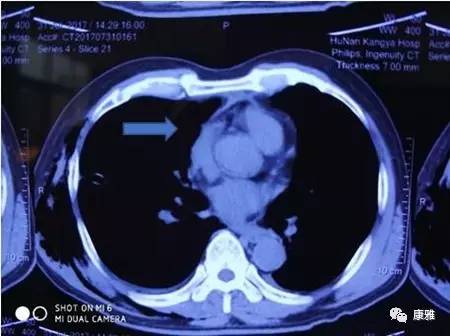

图1术前胸部CT(肿块为箭头所指处))